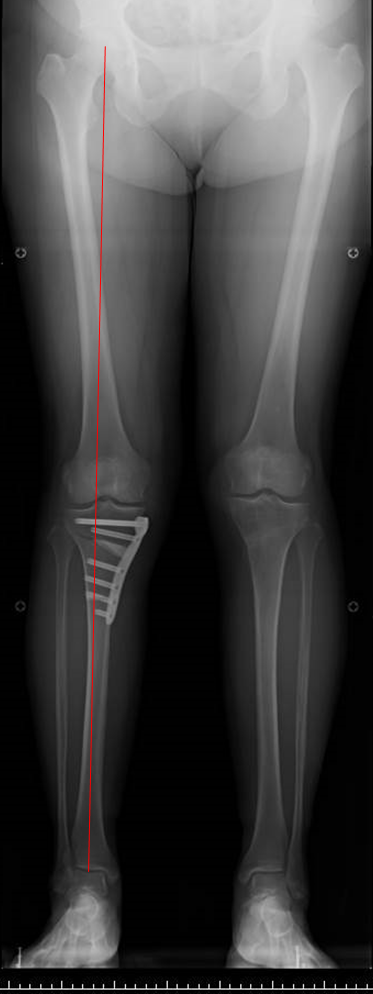

高位脛骨骨切り術

変形性膝関節症の多くは、膝がO脚であるために膝の内側の軟骨が減ることで痛みが生じます。

すねの骨(脛骨)を切って、少しX脚に矯正する手術です。

この手術を行うと膝の内側にかかっていた体重が膝の外側にかかるようになり、痛みが軽減または消失します。

近年では中高年でスポーツをされる方が増えており、そういった方や若年者では自分の膝関節を温存する目的で骨切り術を行っています。